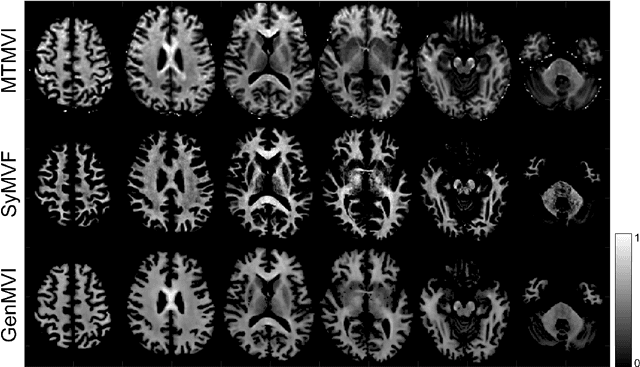

Abstract:Background and Purpose: A current algorithm to obtain a synthetic myelin volume fraction map (SyMVF) from rapid simultaneous relaxometry imaging (RSRI) has a potential problem, that it does not incorporate information from surrounding pixels. The purpose of this study was to develop a method that utilizes a convolutional neural network (CNN) to overcome this problem. Methods: RSRI and magnetization transfer images from 20 healthy volunteers were included. A CNN was trained to reconstruct RSRI-related metric maps into a myelin volume-related index (generated myelin volume index: GenMVI) map using the myelin volume index map calculated from magnetization transfer images (MTMVI) as reference. The SyMVF and GenMVI maps were statistically compared by testing how well they correlated with the MTMVI map. The correlations were evaluated based on: (i) averaged values obtained from 164 atlas-based ROIs, and (ii) pixel-based comparison for ROIs defined in four different tissue types (cortical and subcortical gray matter, white matter, and whole brain). Results: For atlas-based ROIs, the overall correlation with the MTMVI map was higher for the GenMVI map than for the SyMVF map. In the pixel-based comparison, correlation with the MTMVI map was stronger for the GenMVI map than for the SyMVF map, and the difference in the distribution for the volunteers was significant (Wilcoxon sign-rank test, P<.001) in all tissue types. Conclusion: The proposed method is useful, as it can incorporate more specific information about local tissue properties than the existing method.